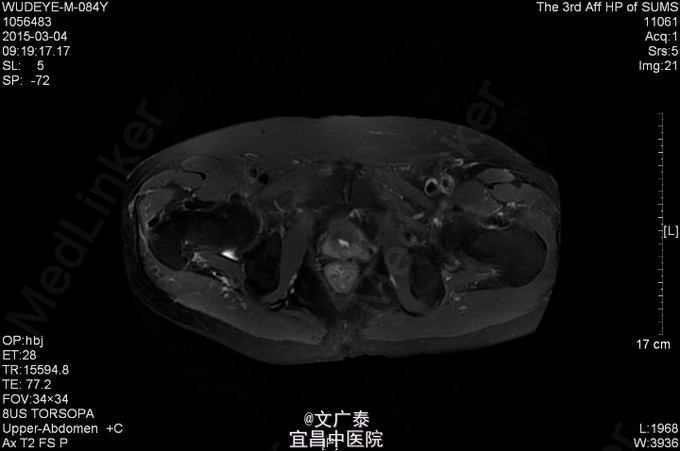

1、TURP加双侧睾丸切除术后11年 2、患者于11年前在本院行前列腺电切术加双侧睾丸切除术后,术后病理回报:前列腺腺癌,(Gleason评分:4+5=9分)。术后予以康士得(50mg qd )内分泌治疗2年后改用福至尔(250mg tid)治疗至今。复查tPSA: 2011.02 tPSA:1.00 ng/L,2012.02 tPSA:0.804 ng/L,2013.02 tPSA:1.23 ng/L,2014.11 tPSA:2.57 ng/L。

3、直肠指检:肛门括约肌正常,前列腺不大,无触痛,表面光滑,质韧,边缘清楚,中央沟存在,未触及明显结节,指套未见染血。余无异常 4、盆腔MR:前列腺癌术后。核素PET/CT全身:1.前列腺癌术后,局部软组织灶,未见明显异常代谢,考虑疤痕形成可能性大;